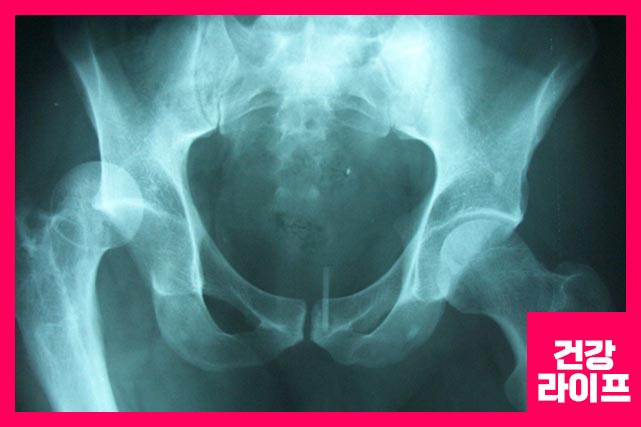

고관절은 볼기뼈의 절구와 넙다리뼈 머리 사이의 활액 관절입니다. 해당 관절은 몸의 안정성과 체중 부하를 위한 기능을 합니다. 구조는 세 가지 유형입니다.

대퇴골 위쪽 1/4이 부러지는 것을 고관절 골절이라고 합니다. 과격한 운동, 낙상(옆으로 넘어졌을 때) 생깁니다.